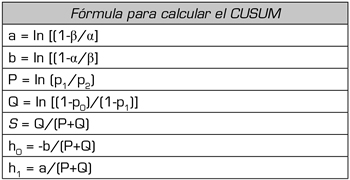

El tipo de test propuesto en nuestro estudio se aplica a conjuntos de datos discretos que toman valores binarios de acuerdo a la ocurrencia o no de un evento (en este caso éxito o fallo de la técnica) y que son recogidos en forma secuencial. La fórmula utilizada en el cálculo del CUSUM se muestra en la Tabla I. La función que define la curva de Cusum en la curva de rendimiento se calcula a partir de las constantes: porcentaje de fallo aceptable (p0) e inaceptable (p1), probabilidad de error Tipo I y II (α y β) a partir de los cuales se calcula el valor de s y los límites de decisión para la hipótesis nula y alternativa h0 y h1 que se mantienen constantes para cualquier valor de la muestra (Tabla I y II). Se tomó como porcentaje de fallo aceptable un 20 % e inaceptable de fallo de 40 % (Tabla II). El error α y β se tomó como 0,1.

Tabla I. Variables que se utilizan para el cálculo de las bandas de decisión (h0 y h1) y el valor de s a partir de los índices aceptables e inaceptables de fallo (p0 y p1) y el error tipo I y II (α y β)